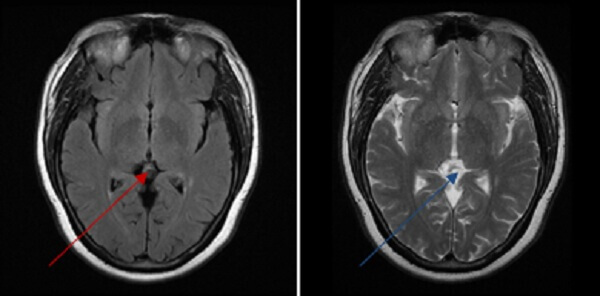

Figure 1: (a,red arrow) axial FLAIR demonstrates a mildly hyperintense pineal mass which is hyperintense on T2 (b,blue arrow) and which has a thin rim of contrast enhancement (c, green arrow).

Pineal cyst is by far the most common pineal lesion. Pineal cysts displace pineal calcifications, are generally less than 10 mm, have homogenous T2 hyperintense signal iso to slightly hyperintense to CSF on MRI and mildly hyperintense on FLAIR. Pineal cysts typically demonstrate thin walled enhancement, although nodular or thicker enhancement of the wall is possible and the central cystic area may fill in with contrast on delayed imaging. The normal enhancing pineal gland may also be seen, typically posterior to the cyst. Differentiating between a pineal cyst and a very indolent pineoblastoma can be a diagnostic challenge; however, pineal cysts are far more common and cysts with classical features are incidental findings that do not require treatment or follow up.